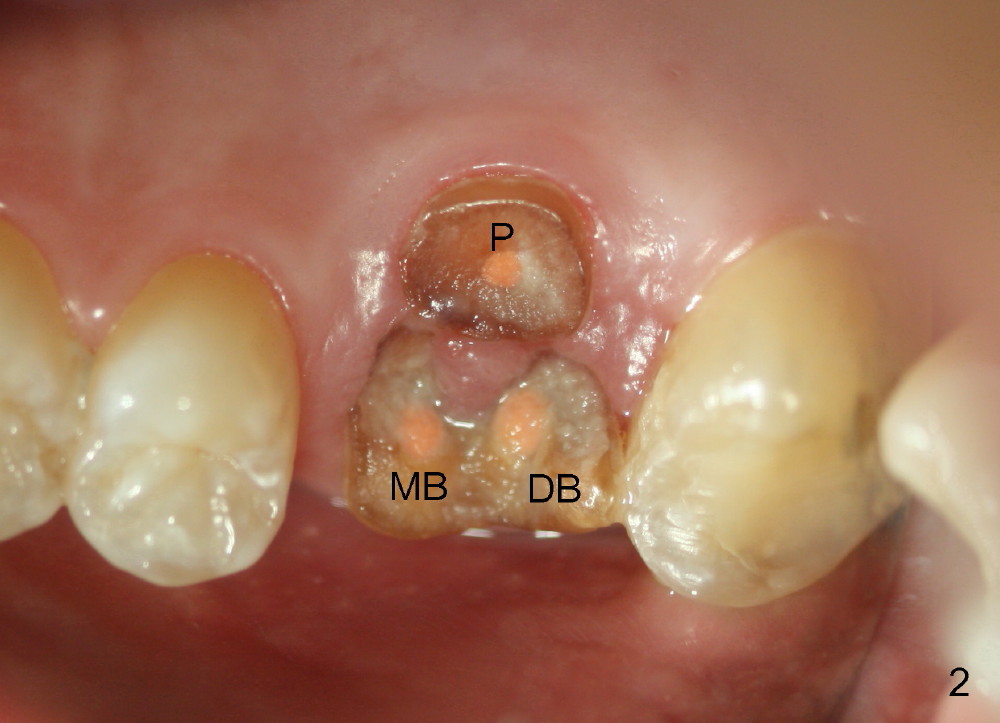

The 1st approach is used for the following case: a 46-year-old man with #14 (Fig.1). The root stumps are large and relatively close to each other (Fig.2 mirror view) so that when the roots are extracted (Fig.3 black), the septum is narrow (white). A 1.2 mm pilot drill penetrates the septum (red).